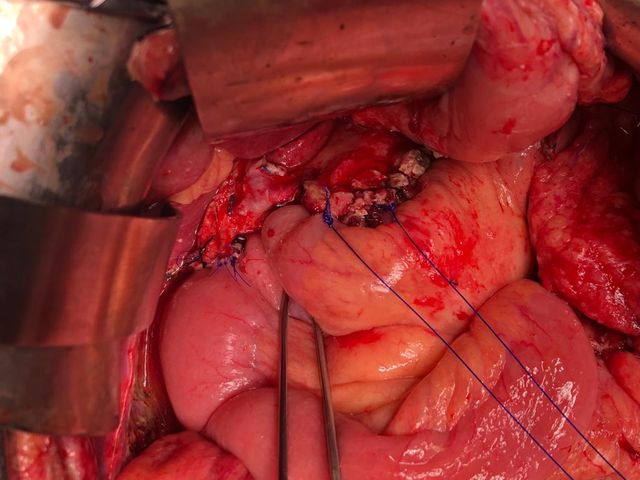

Challenging emergency during the COVID: Child’s A CLD with HUGE gastric varices uncontrolled

Child’s A CLD with HUGE gastric varices uncontrolled by Endoscopic glue and attempted EUS coiling. One salvage option would be TIPSS with balloon vascular occlusion but due to logistics we went for modified sugiura procedure. Splenectomy + Gastro esophageal devascularisation with anterior Gastrotomy and overseeing of gastric varices with pyloroplasty. Images show 1 CECT showing large gastric fundal varices. 2,3,4 Gastro Esophageal devasc 5, 6 Large fundal varices before and after oversewing. 7. Anterior gastrotomy 8. Pyloroplasty. Postoperative recovery was uneventful.